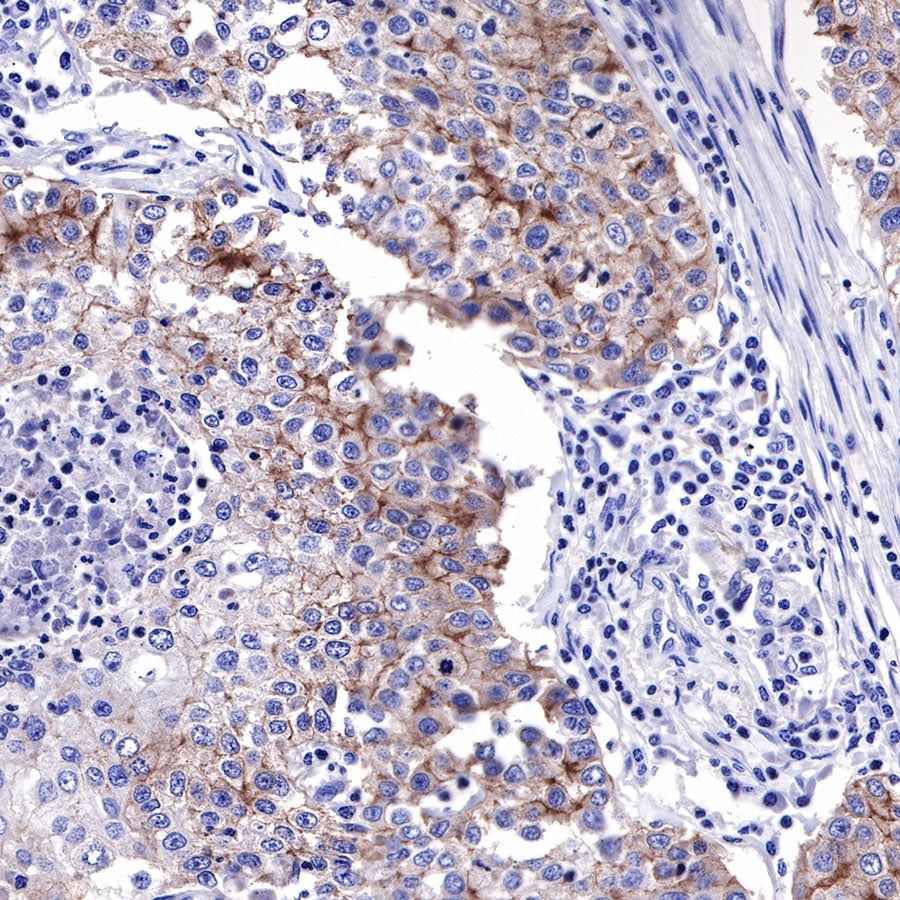

Immunohistochemistry

IHC shows positive staining in paraffin-embedded human cervical squamous cell carcinoma. Anti-EGFR antibody was used at 1/2000 dilution, followed by a HRP Polymer for Mouse & Rabbit IgG (ready to use). Counterstained with hematoxylin. Heat mediated antigen retrieval with Tris/EDTA buffer pH9.0 was performed before commencing with IHC staining protocol.